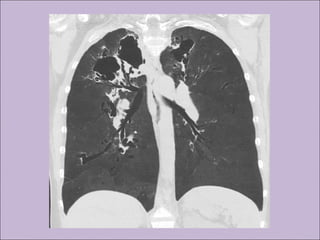

C) Anormalidades persistentes à radiografia de tórax

Bronquiectasias

Manifestações sino-pulmonaresManifestações sino-pulmonares A)Colonização / infecção persistentes por patógenos típicos da FC como Staphylococcus aureus, Haemophilus influenzae, Pseudomonas aeruginosa e Burkholderia cepacia B) Tosse crônica e produtiva C) Anormalidades persistentes à radiografia de tórax D) Obstrução das vias aéreas E) Pólipos nasais, sinusite F) Baqueteamento digital Rosenstein. J Pediatr. 1998;132:389-95

COMPLICAÇÕES DA FIBROSECÍSTICA RESPIRATÓRIAS Bronquiectasias Atelectasias Hemoptise Pneumotórax Pólipos nasais Sinusite Hiperreatividade Cor Pulmonale Ins. Respiratória Impactação mucóide ABPA GASTROINTESTINAIS Íleo meconial Peritonite meconial SOID Prolapso retal Intussucepção Volvo intestinal Colonopatia fibrosante Apendicite Atresia intestinal Pancreatite(s) Cirrose biliar Icterícia neonatal colestática Esteatose hepática DRGE Colelitíase Failure to thrive Def vits ADEK In Pancreática Diabetes OUTRAS Infetilidade Atraso puberal Edema-hipoproteinemia Desidratação grave/choque Osteoartropatia hipertrófica Baqueteamento digital Amiloidose Diabetes mellitus Kliegman: Nelson Textbook of Pediatrics, 18th ed., 2007